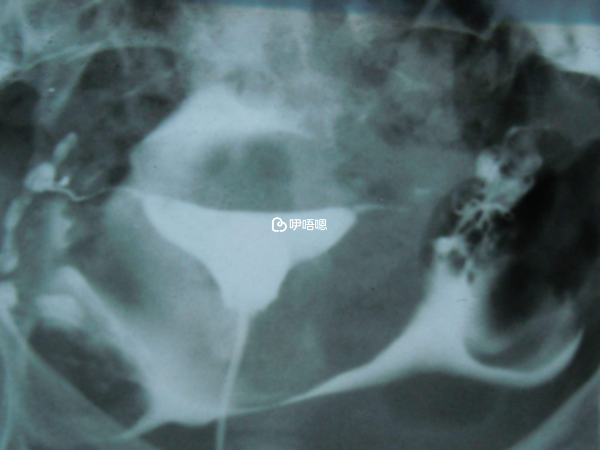

經過一個多月的學習,我高度懷疑我有多囊。這次問診也學聰明瞭,醫生問試了多久,我就撒謊說一年多了,並告訴她我覺得我有多囊。她終於開了單子查激素做b超,並讓我老公也去檢查。老公的結果出來一點沒問題。我的激素查出來正常,雖然fsh和lh比值已近2,多囊症狀之一。

b超沒有太多小卵泡,但右側卵巢大於10立方厘米,也是多囊症狀之一。醫生話說得非常含糊,沒有給我確診多囊,只說有可能,我說看我的排卵試紙和體溫,排卵就是有問題啊,她就一直說“可能吧,是啊,也許是多囊”。

醫生根據我之前做過的所有檢查,確定了一套方案,來曲唑促排+打破卵針+人工受精。整個流程和國內略有不同,比如說,國內一般會先讓吃促排藥,然後自己回家同房,試幾個月不行才會考慮人授。再比如說,國內要求人授前必須查輸卵管,而這裡說試一次不成再查。聽說造影很疼,還好沒受那個罪。